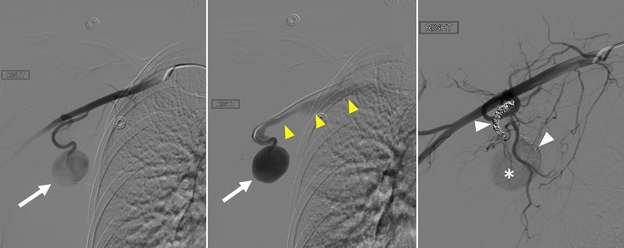

Figure 5B. Pseudoaneurysm. Pre-treatment selective catheter-directed digital subtraction angiography (left, middle) in the interventional suite confirmed the presence of a large pseudoaneurysm (arrows) fed by a branch of the right axillary artery. Post-treatment angiography (right) status post coil embolization of two identified feeding branches (white arrowheads) demonstrates faint residual filling of the sac (asterisk). During the intervention, it was noted that the pseudoaneurysm had an associated outflow tract with brisk drainage via the right axillary vein (yellow arrowheads), consistent a concomitant iatrogenic arteriovenous fistula (AVF).